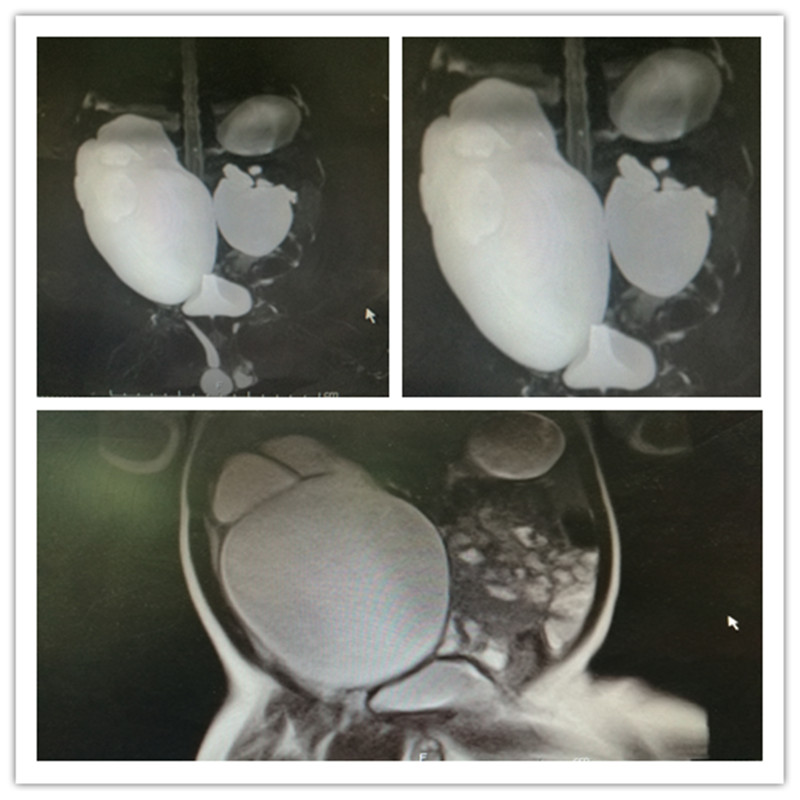

近日,我院泌尿外科收治一位出生45天的婴儿,这也是目前为止,在我院泌尿外科住院完成手术最小的患儿。主因患儿家长6月前孕检时发现患儿双侧肾积水,曾就诊于北京某医院,建议开放手术,后经人介绍来我院就诊。检查结果显示患儿双肾积水,右侧较为严重。由于患儿年幼,无形中给治疗、麻醉和手术增加了很多困难。